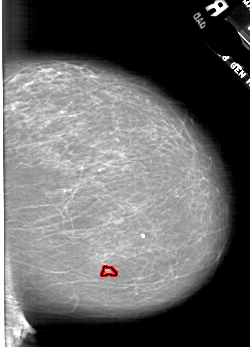

A_1773_1.RIGHT_MLO

RIGHT_MLO LINES 6766 PIXELS_PER_LINE 4276 BITS_PER_PIXEL 12 RESOLUTION 43.5 OVERLAY

FILE: A_1773_1.RIGHT_MLO.OVERLAY

TOTAL_ABNORMALITIES 1

ABNORMALITY 1

LESION_TYPE CALCIFICATION TYPE PLEOMORPHIC DISTRIBUTION CLUSTERED

ASSESSMENT 4

SUBTLETY 2

PATHOLOGY BENIGN

TOTAL_OUTLINES 1

BOUNDARY